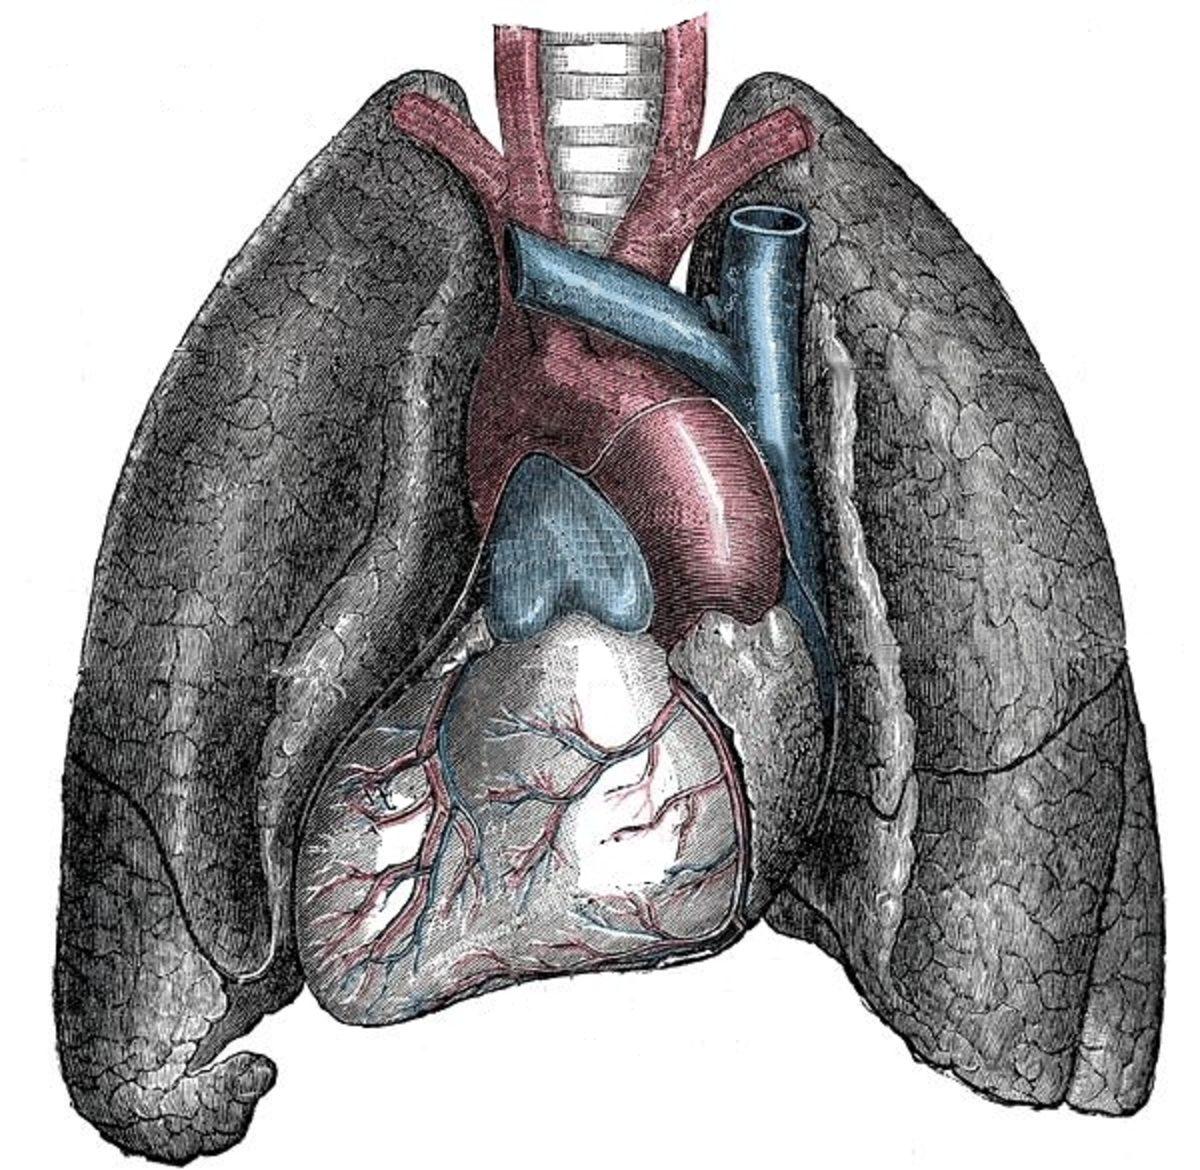

Organların değişimine göre de genetik bozukluğun ismi situs inversus, sadece iç organların ayna görünümünde olmasını ifade ediyor. Situs inversus totails (SIT) ise iç organların yanı sıra kalbin de ters konumda olması. Dekstrokardi yani sağkalplilikte kalp, solda değil sağ göğüste bulunuyor.

İç organların ters olup kalbin normal olmasında ise riskli durumlar olabildiği için kişilerin ameliyat olması gerekebilir. Organların yerinin tam belli olmadığı hastaların ise medikal sorunlarla karşılaşma ihtimali SIT hastalarına göre daha fazla.